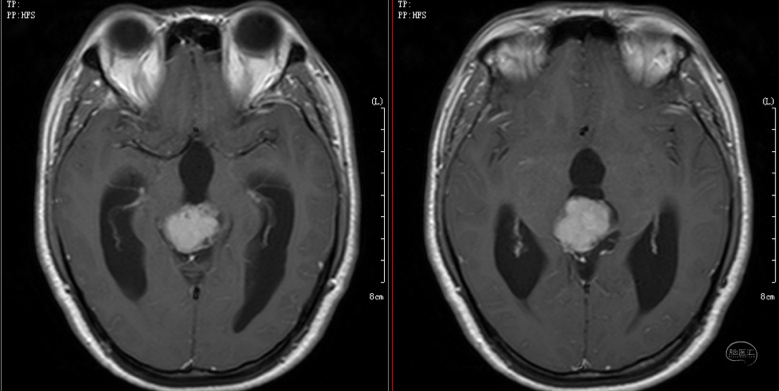

第一次术前MRI-松果体区占位,幕上脑室扩张明显,第三脑室底下疝入鞍内,蝶鞍扩大

第一次术前MRI-松果体区占位,幕上脑室扩张明显,第三脑室底下疝入鞍内,蝶鞍扩大